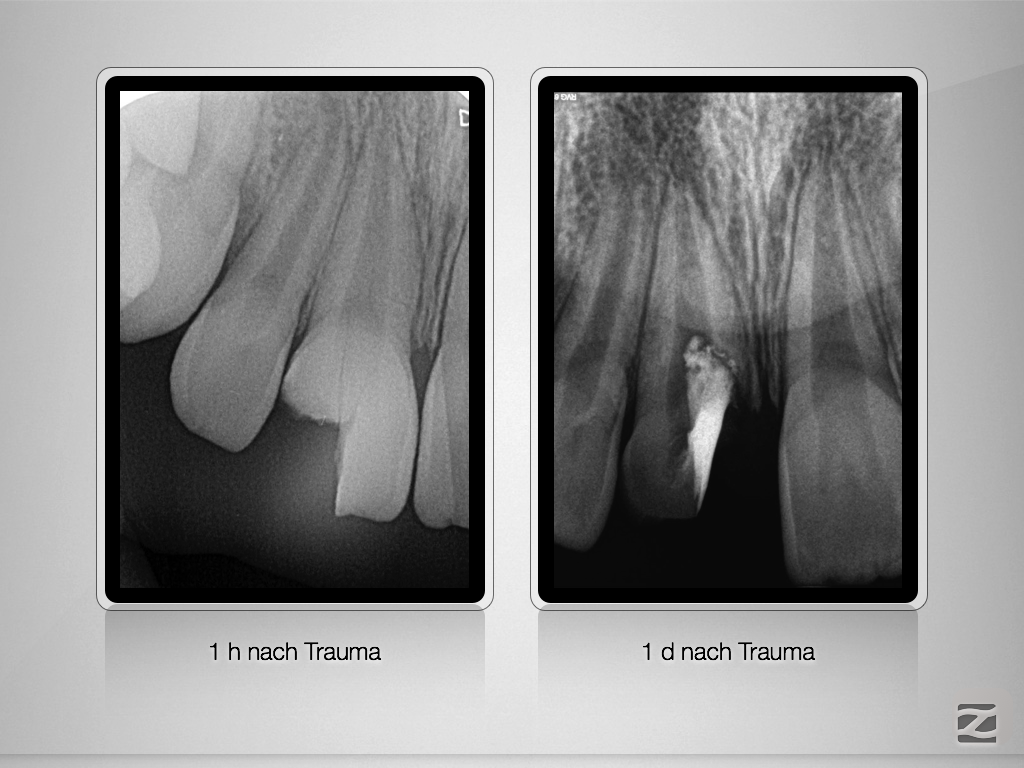

Komplizierte Kronen-Wurzelfraktur